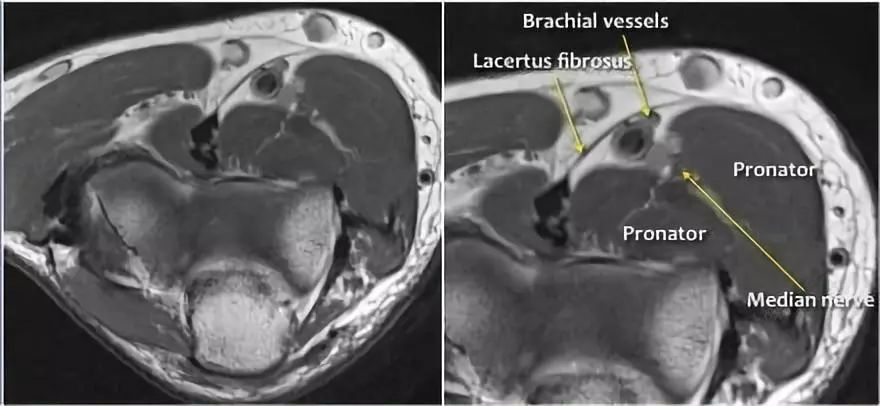

中位神经:正中神经落后于Lacertus纤维,即肱二头肌的腱膜并穿透旋前肌。